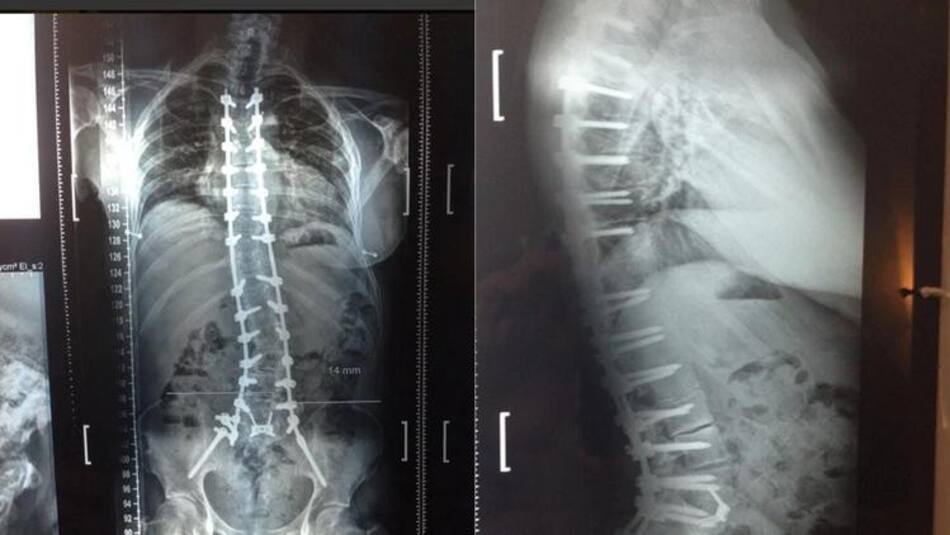

Radiografías practicadas a Ricardo Fort.

En abril de ese año fue operado de esa maldita rodilla: "Fue doloroso, la verdad. Gracias a los calmantes puedo aguantar el dolor y mañana empezaremos con la kinesiología para empezar a mover la pierna y caminar de a poco con muletas", contaría Fort.

La última operación a la que se sometió fue en septiembre: le implantaron 16 tornillos de titanio en la columna, más dos varillas para apuntalarla, y anillos de metal para separar las vértebras y evitar el desgaste de los discos. Aquella cirugía llevó nueve horas, y aunque todo salió bien los problemas no tardaron en llegar luego de que su organismo rechazara los cuerpos extraños, ocasionándole aún más problemas.